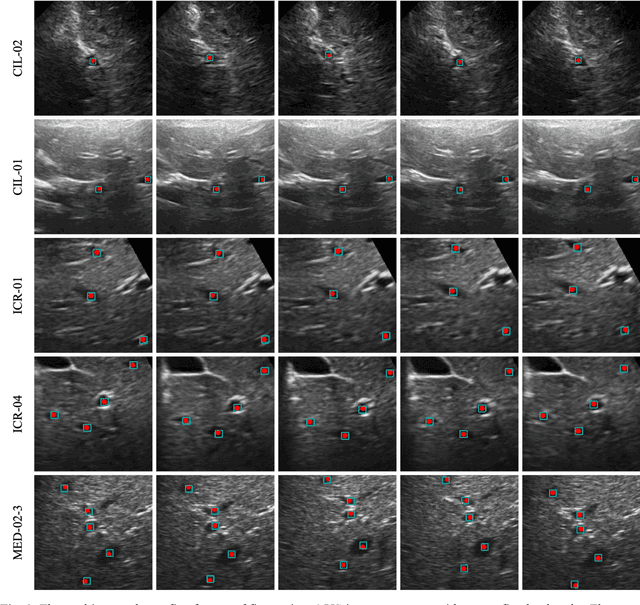

Abstract:This study proposed a deep learning-based tracking method for ultrasound (US) image-guided radiation therapy. The proposed cascade deep learning model is composed of an attention network, a mask region-based convolutional neural network (mask R-CNN), and a long short-term memory (LSTM) network. The attention network learns a mapping from a US image to a suspected area of landmark motion in order to reduce the search region. The mask R-CNN then produces multiple region-of-interest (ROI) proposals in the reduced region and identifies the proposed landmark via three network heads: bounding box regression, proposal classification, and landmark segmentation. The LSTM network models the temporal relationship among the successive image frames for bounding box regression and proposal classification. To consolidate the final proposal, a selection method is designed according to the similarities between sequential frames. The proposed method was tested on the liver US tracking datasets used in the Medical Image Computing and Computer Assisted Interventions (MICCAI) 2015 challenges, where the landmarks were annotated by three experienced observers to obtain their mean positions. Five-fold cross-validation on the 24 given US sequences with ground truths shows that the mean tracking error for all landmarks is 0.65+/-0.56 mm, and the errors of all landmarks are within 2 mm. We further tested the proposed model on 69 landmarks from the testing dataset that has a similar image pattern to the training pattern, resulting in a mean tracking error of 0.94+/-0.83 mm. Our experimental results have demonstrated the feasibility and accuracy of our proposed method in tracking liver anatomic landmarks using US images, providing a potential solution for real-time liver tracking for active motion management during radiation therapy.